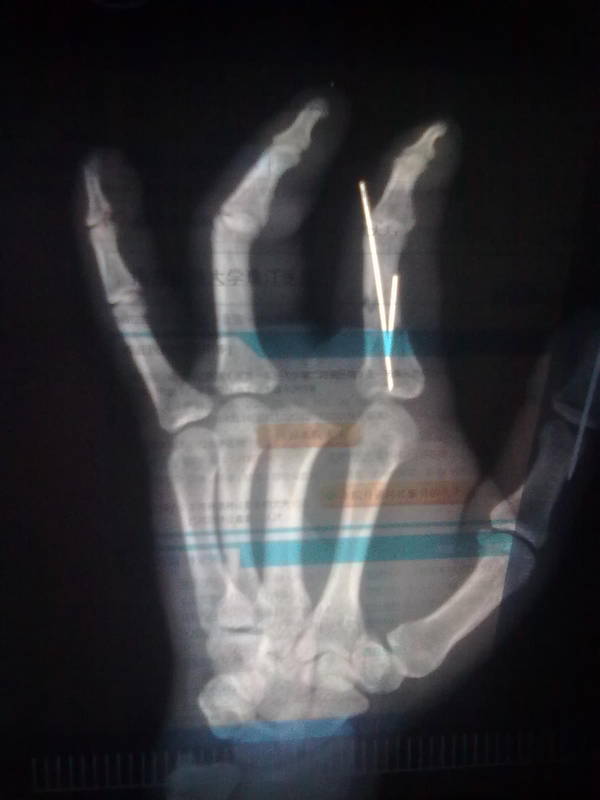

全形再造之示中指全形再造

尊敬的咨询医生那你好本人何快兵21岁湖南郴州汝城人现今在广州于今年手指被大型折弯机压成重伤,由于这里医疗条件不好只能做截指手术现已做好但是希望哪位名医教授否做再造或移植手术,请用你的高超精湛的医术能否帮忙,有没有兴趣来攻克这个难关,谢谢

拍片